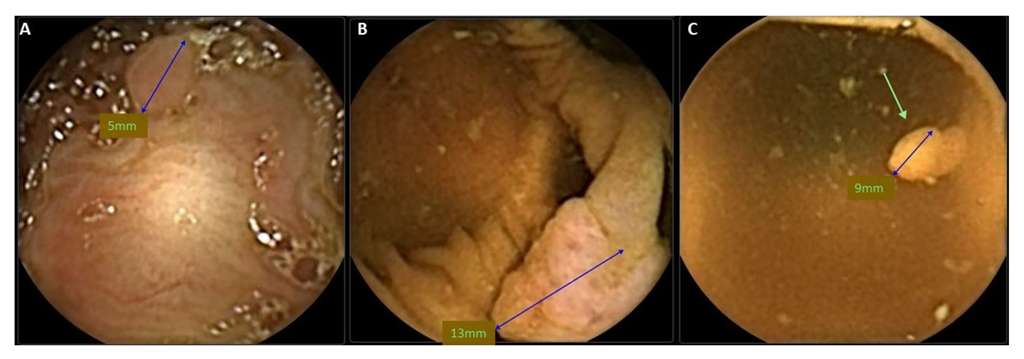

4. CCE-2 and Flat Polyps